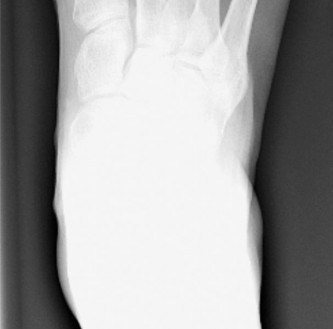

- Radiographic Evaluation:

- Weight-Bearing X-rays: Essential for proper classification and surgical planning. Obtain standard views:

- Anteroposterior (AP): Measure the 4-5 intermetatarsal angle (IMA, normal < 8-9 degrees), assess the contour of the fifth metatarsal head, and evaluate the lateral bowing of the fifth metatarsal shaft.

- Lateral: Assess the fifth metatarsal head articulation and any plantarflexion of the fifth metatarsal.

- Oblique: Provides the best view of the lateral condyle of the fifth metatarsal head and shaft for Type I bunionettes. This view is crucial for identifying the extent of hypertrophy.